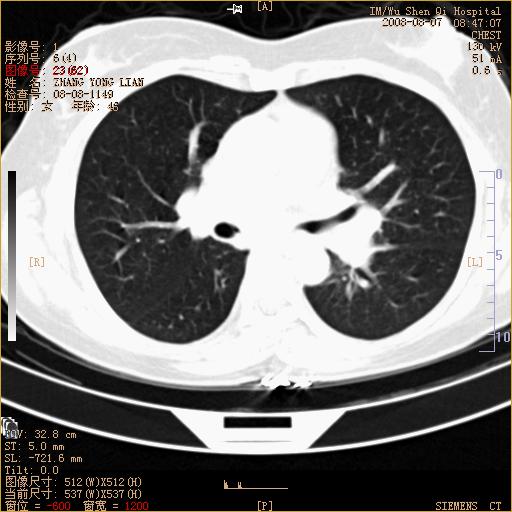

标题: CT15050:女,46岁,咳嗽胸痛一月余 [打印本页]

纵隔窗没发全,左下肺近胸膜处结节。有长毛刺,纵隔淋巴结增大,不排除恶性病变。

考虑肺癌

考虑左肺下叶后基底段周围型肺癌伴纵隔淋巴结转移可能性大。

左下肺ca并纵隔及左肺门区淋巴结转移。

1)考虑左肺下叶后基底段周围型肺癌伴纵隔淋巴结转移。2)脾内低密度灶,性质待定;不排除转移瘤可能。